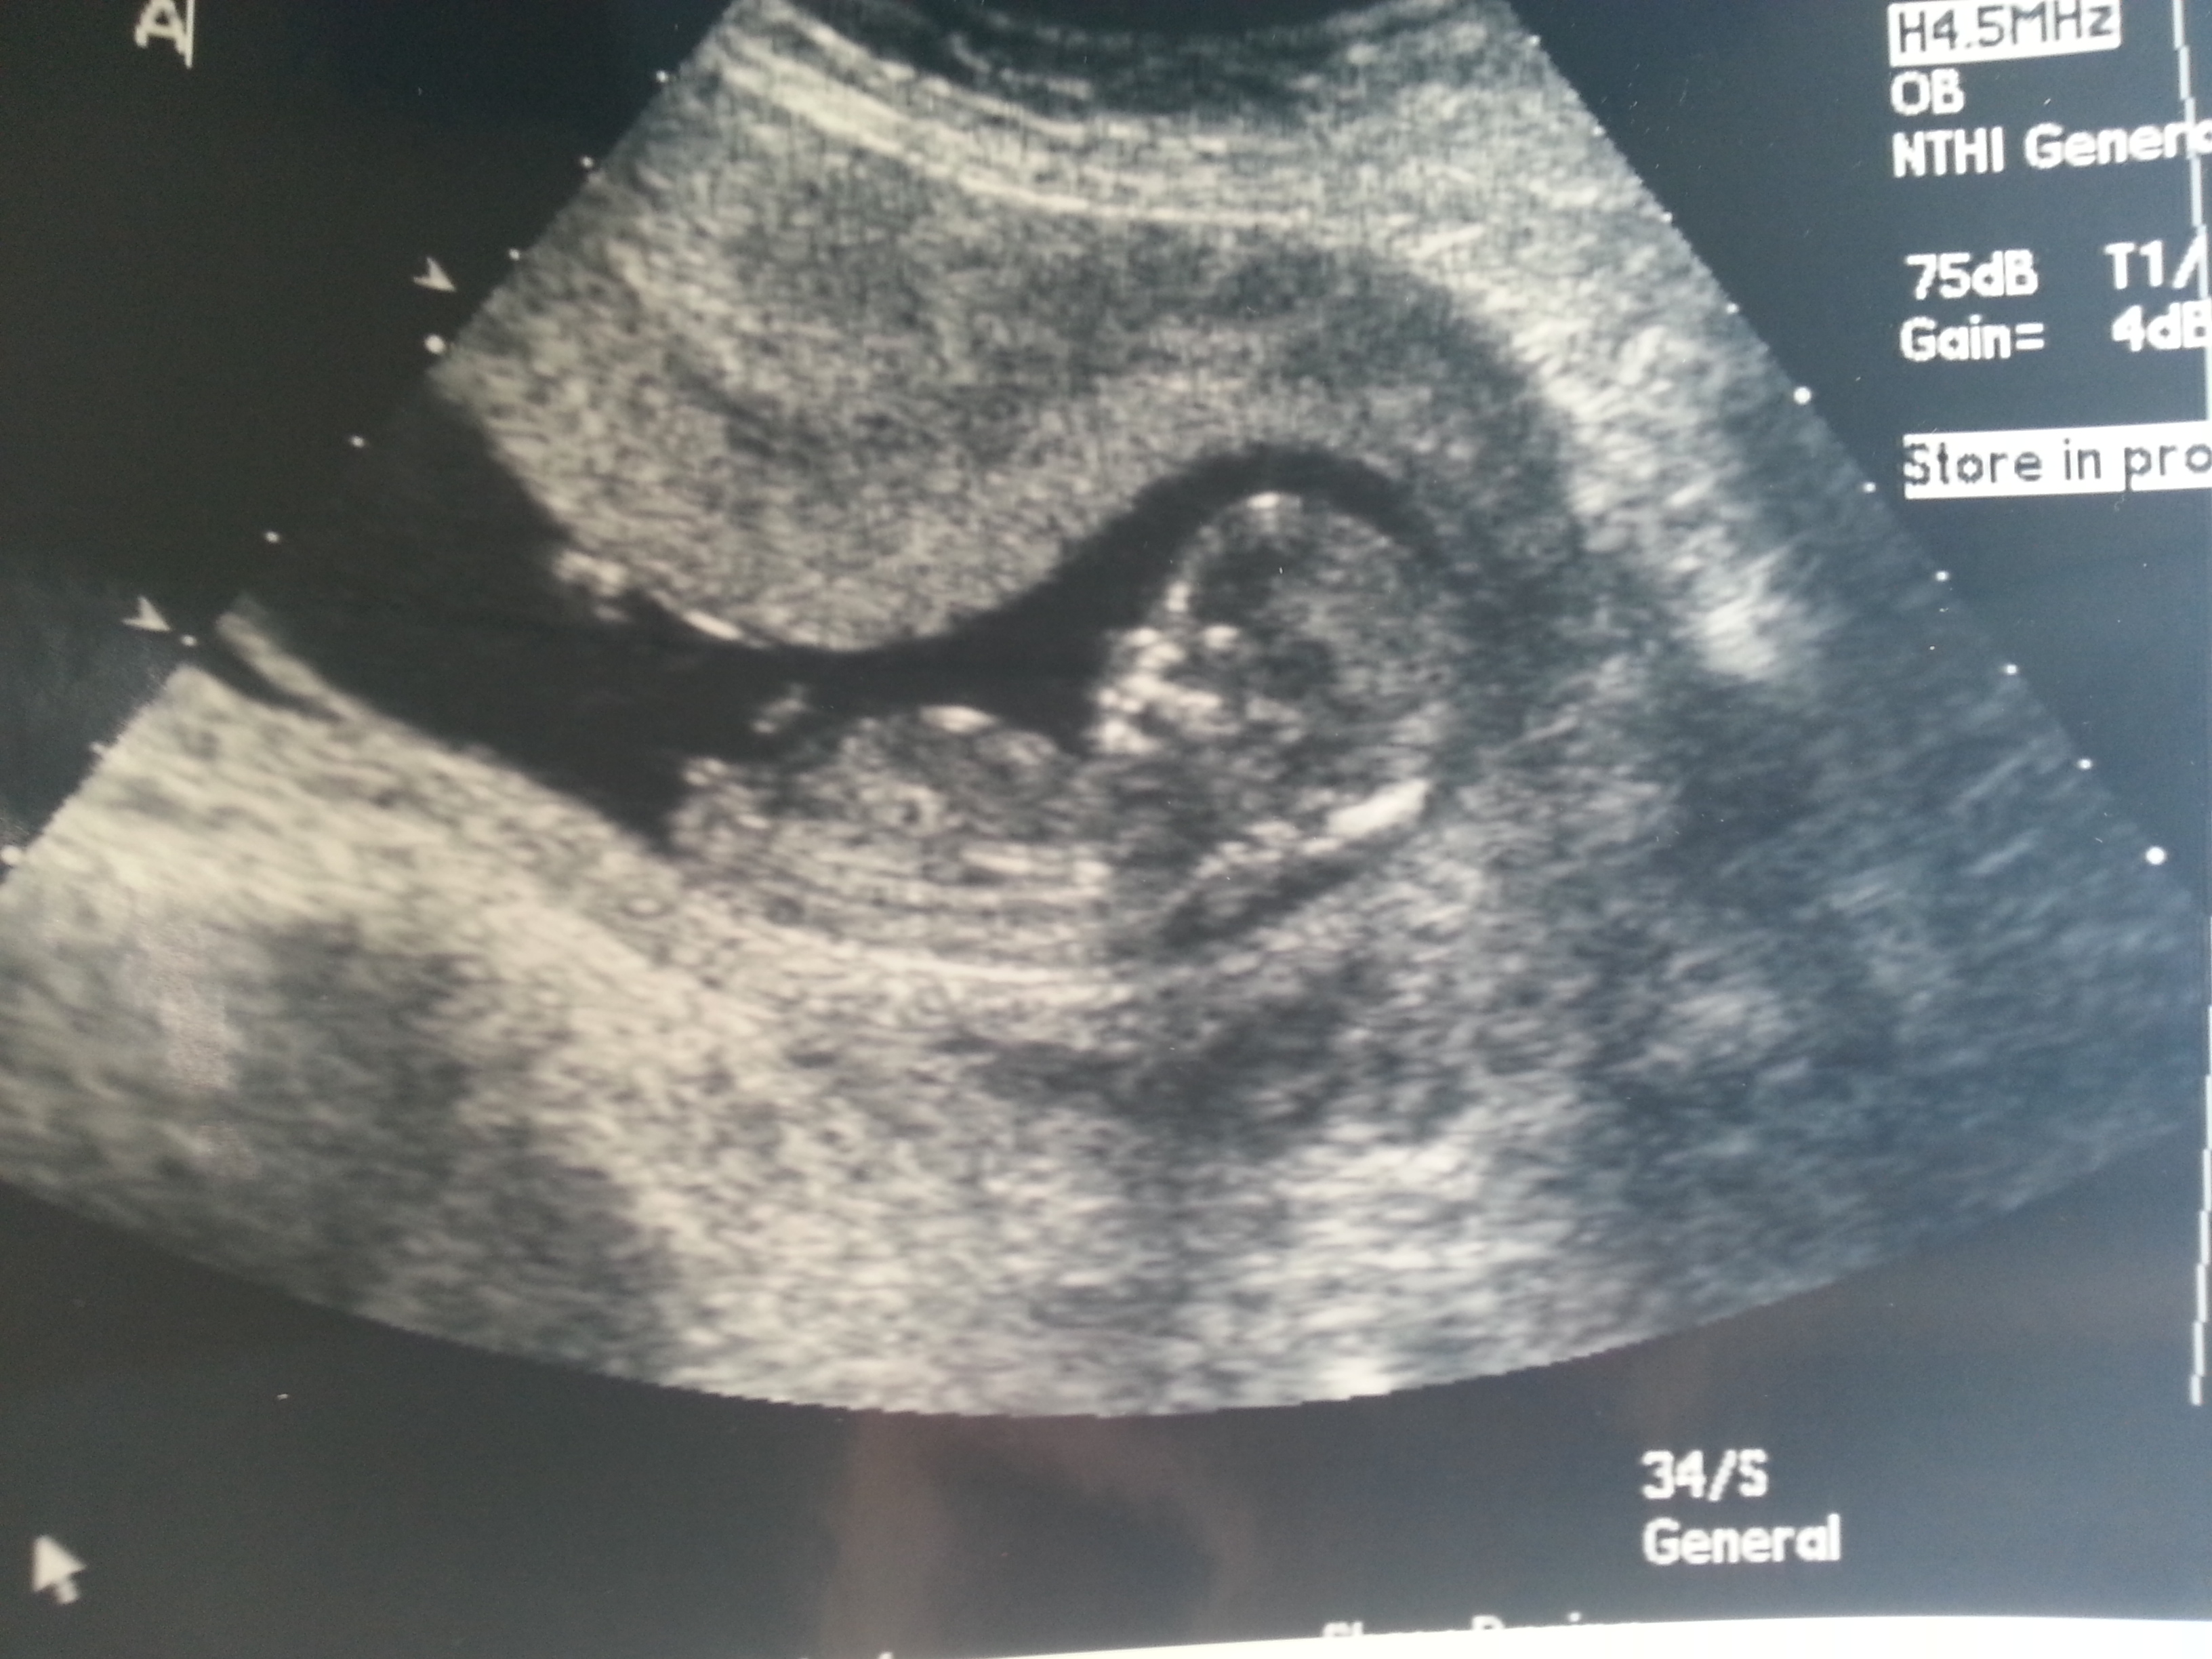

I was 12weeks 6 days and measuring 13weeks 3 days.

Maybe boy/girl. Not the best shots though!

I think B is a boy and A is a girl.

I think B is a boy, A could go either way but I lean boy.